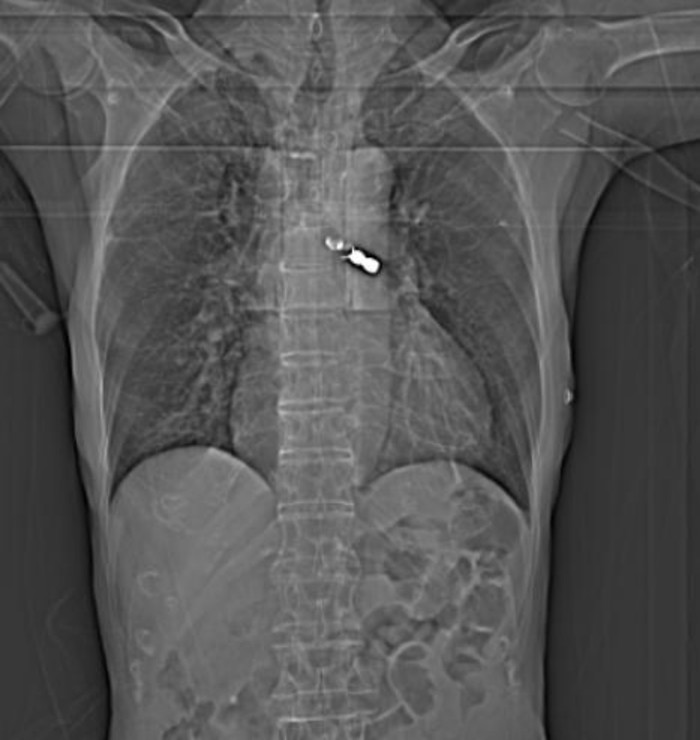

Người bệnh được chuyển tới khoa Nội Hô hấp – Tiêu hóa Bệnh viện đa khoa tỉnh Phú Thọ. Sau khi nhập viện bệnh nhân được chỉ định các xét nghiệm cấp cứu, chụp CT ngực không tiêm thuốc cản quang. Kết quả chụp: dị vật nghi cung răng giả vị trí phế quản gốc trái.

Người bệnh đã được hội chẩn cùng với kíp nội soi phế quản, đã tiến hành nội soi phế quản ống mềm gây tê cho người bệnh đã gắp thành công dị vật là cung răng giả.